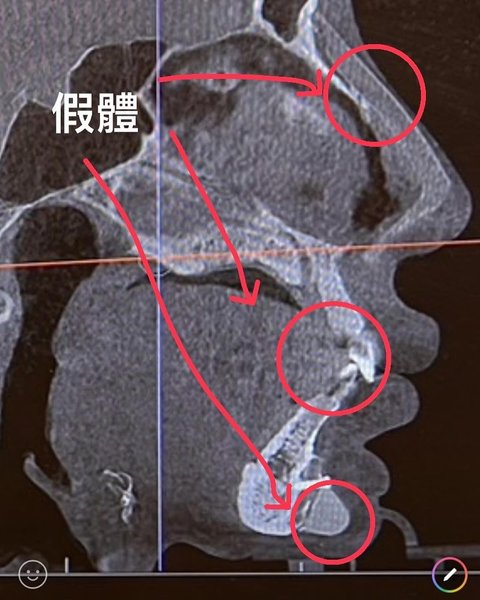

Загалом модель, відома під псевдо Спрайт, лишилась задоволеною своїми зовнішніми трансформаціями, якби не цей прикрий інцидент. Під час спроби пройти через сканер безпеки апарат зафіксував хірургічний гвинт трохи нижче її нижньої губи. Ймовірно, інструмент залишився там під час "протезування підборіддя", яке Фан Ціюань зробила вісім років тому.

На жаль, це був не єдиний хірургічний предмет, який помітили на комп'ютерній томографії.

"Я несподівано виявила, що у мене також є цвяхи в носі. Моє обличчя схоже на пазл", — розповіла модель, опублікувавши фотографії.

Ймовірно, інструмент залишився там під час "протезування підборіддя", яке Фан Ціюань зробила вісім років тому